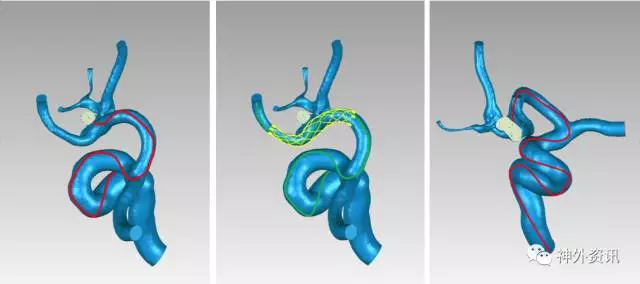

2. 椎动脉迂曲,病变血管迂曲严重伴狭窄,需要导引导管提供高稳定性和支撑力。 选择使用Envoy DA。

(左:Envoy DA导引导管-右侧椎动脉V3段;右:支架导管成功超选左侧大脑后动脉)

所以选择使用Envoy DA

(Envoa DA导引导管—左侧颈内动脉海绵窦段)

(治疗中,ENVOY DA导引导管置于左侧大脑前动脉A1段)

(SONIC 导管顺利超选至畸形血管巢,并且拔管顺利)

(挑战:终末血管供血,超选距离遥远,途经血管迂曲,选择使用Envoy DA)

(Envoy DA导引导管—右侧大脑前动脉A1段)

(成功超选,栓塞后拔管顺利)

1. Envoy DA远端通路导引导管,是强生公司在Envoy导引导管的基础上研发的产品,在保留Envoy近端支撑力的同时,柔软的8cm柔软段能很好的锚定在迂曲的颅内血管中。对于绝大部分的神经介入复杂治疗不需要使用长鞘,为手术提供了便利。

2. 病变血管迂曲的复杂动脉瘤、终末支血管供血的AVM一直是神经介入手术的治疗难点,远端通路导引导管Envoy DA能够为微导管提供更好的稳定性和支撑力,为这类手术的成功治疗提供了保障。